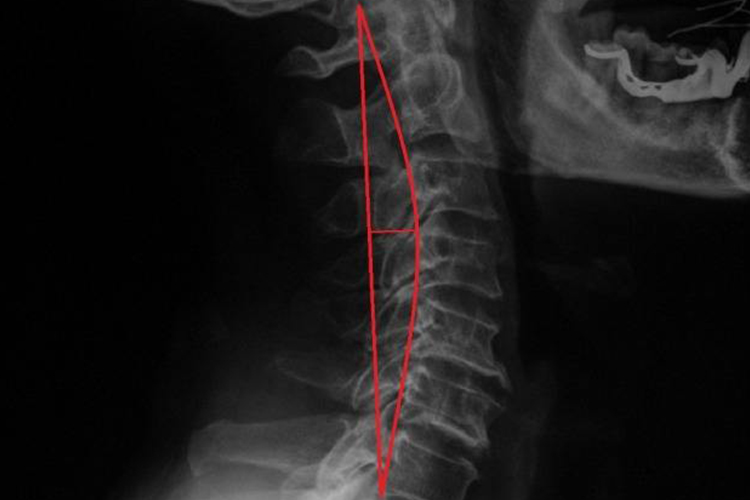

正常颈椎:颈椎共有7个,其主要特征是横突上有一圆孔,称为横突孔。椎体小,椎孔较大,呈三角形。颈椎上下关节突的关节面基本上呈水平位。第2-6颈椎的棘突较短,末端分叉。颈椎总体向前突出,有一定的生理曲度,正常的颈椎间隙纤维环是完整形态,髓核没有膨胀或者突出。

突出颈椎:多由颈部创伤、退行性改变等因素导致,颈椎间盘变性、压缩、纤维环破裂及髓核脱出,刺激或压迫颈椎动脉、脊神经、脊髓等,可引起头痛、眩晕、颈部酸胀等症状。